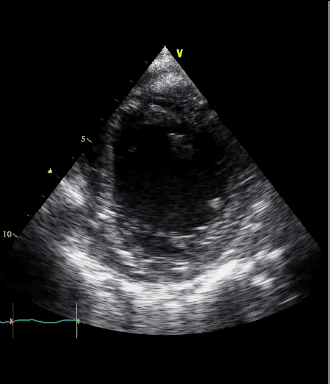

PSAX view

In this PSAX view, no muscular activity is seen in the heart. The absence of contraction in the ventricular walls confirms a state of cardiac standstill. This view emphasizes the lack of cardiac output, supporting the diagnosis of cardiac arrest.